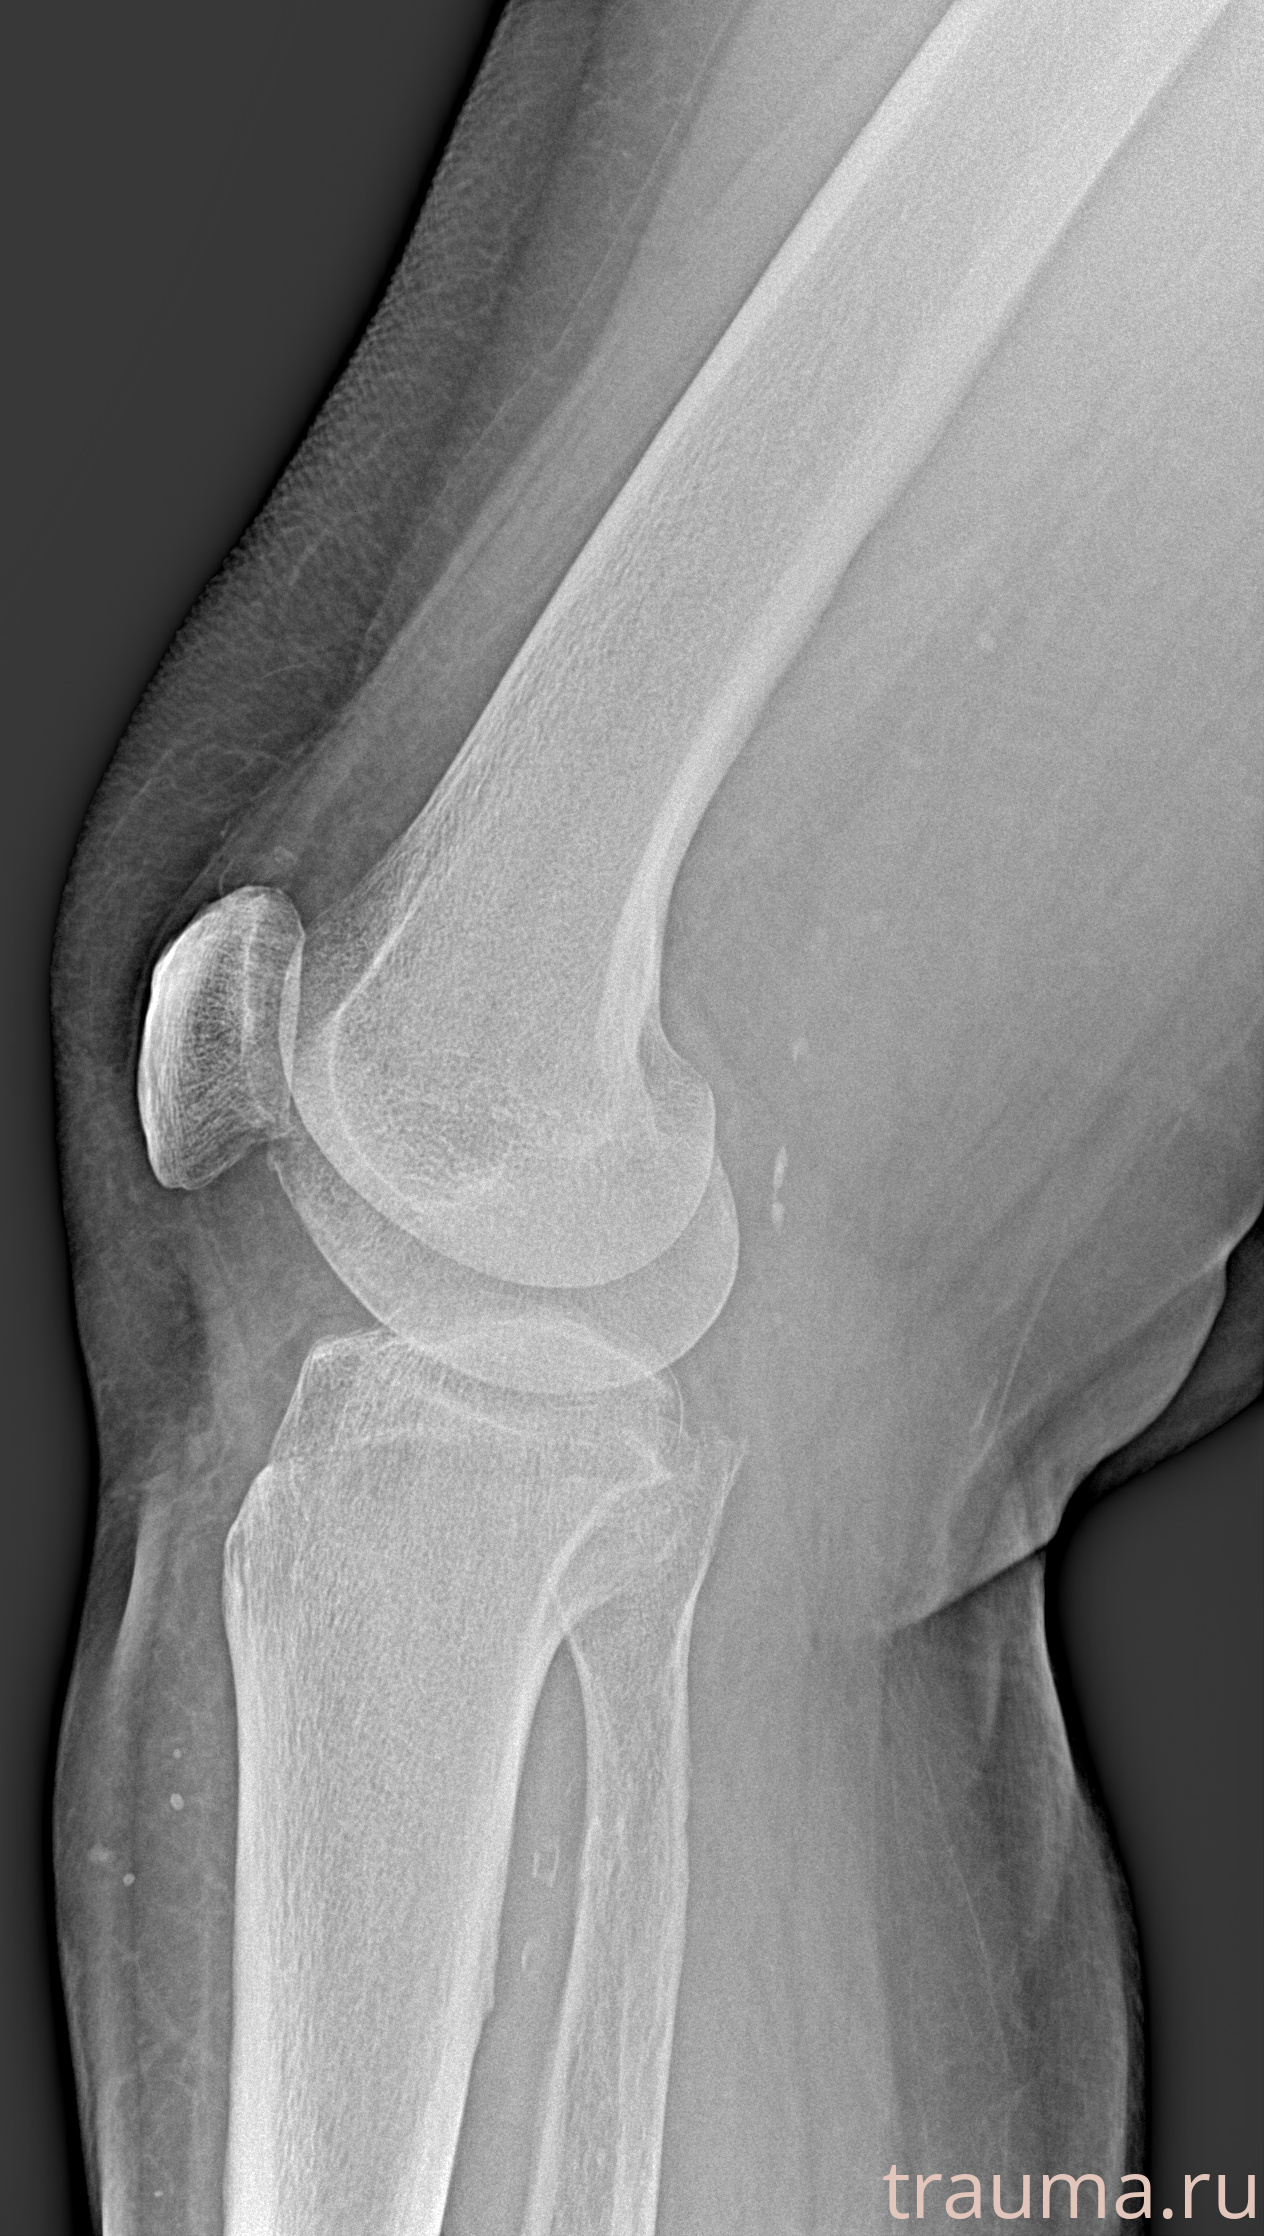

Правая

Рентгенограммы

Рентген на дому: по вашему адресу приезжает врач-рентгенолог, травматолог-ортопед с мобильным рентгеновским аппаратом, проводит диагностику травмы или заболевания, делает необходимые рентгенограммы, дает рекомендации по дальнейшему лечению. Получить качественные снимки в домашних условиях возможно благодаря уникальной методике, разработанной МосРентген Центром для института  Склифосовского